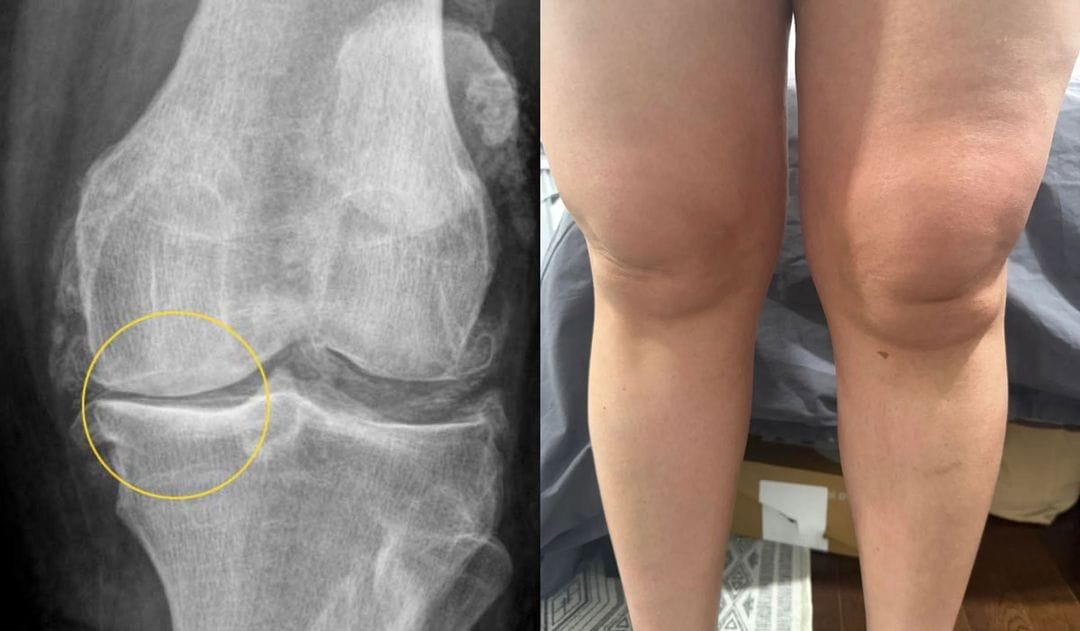

The next day, I examined Marion in my practice.

When the MRI images appeared on the monitor, I was shocked:

Significant osteoarthritis in the knee, first signs also in the hip.

Marion's knee in an inflamed state

Marion looked at the pictures and said, “Tell me honestly, how bad is it?”

I didn’t know what to say. I usually only see this stage in people aged 65 and over.